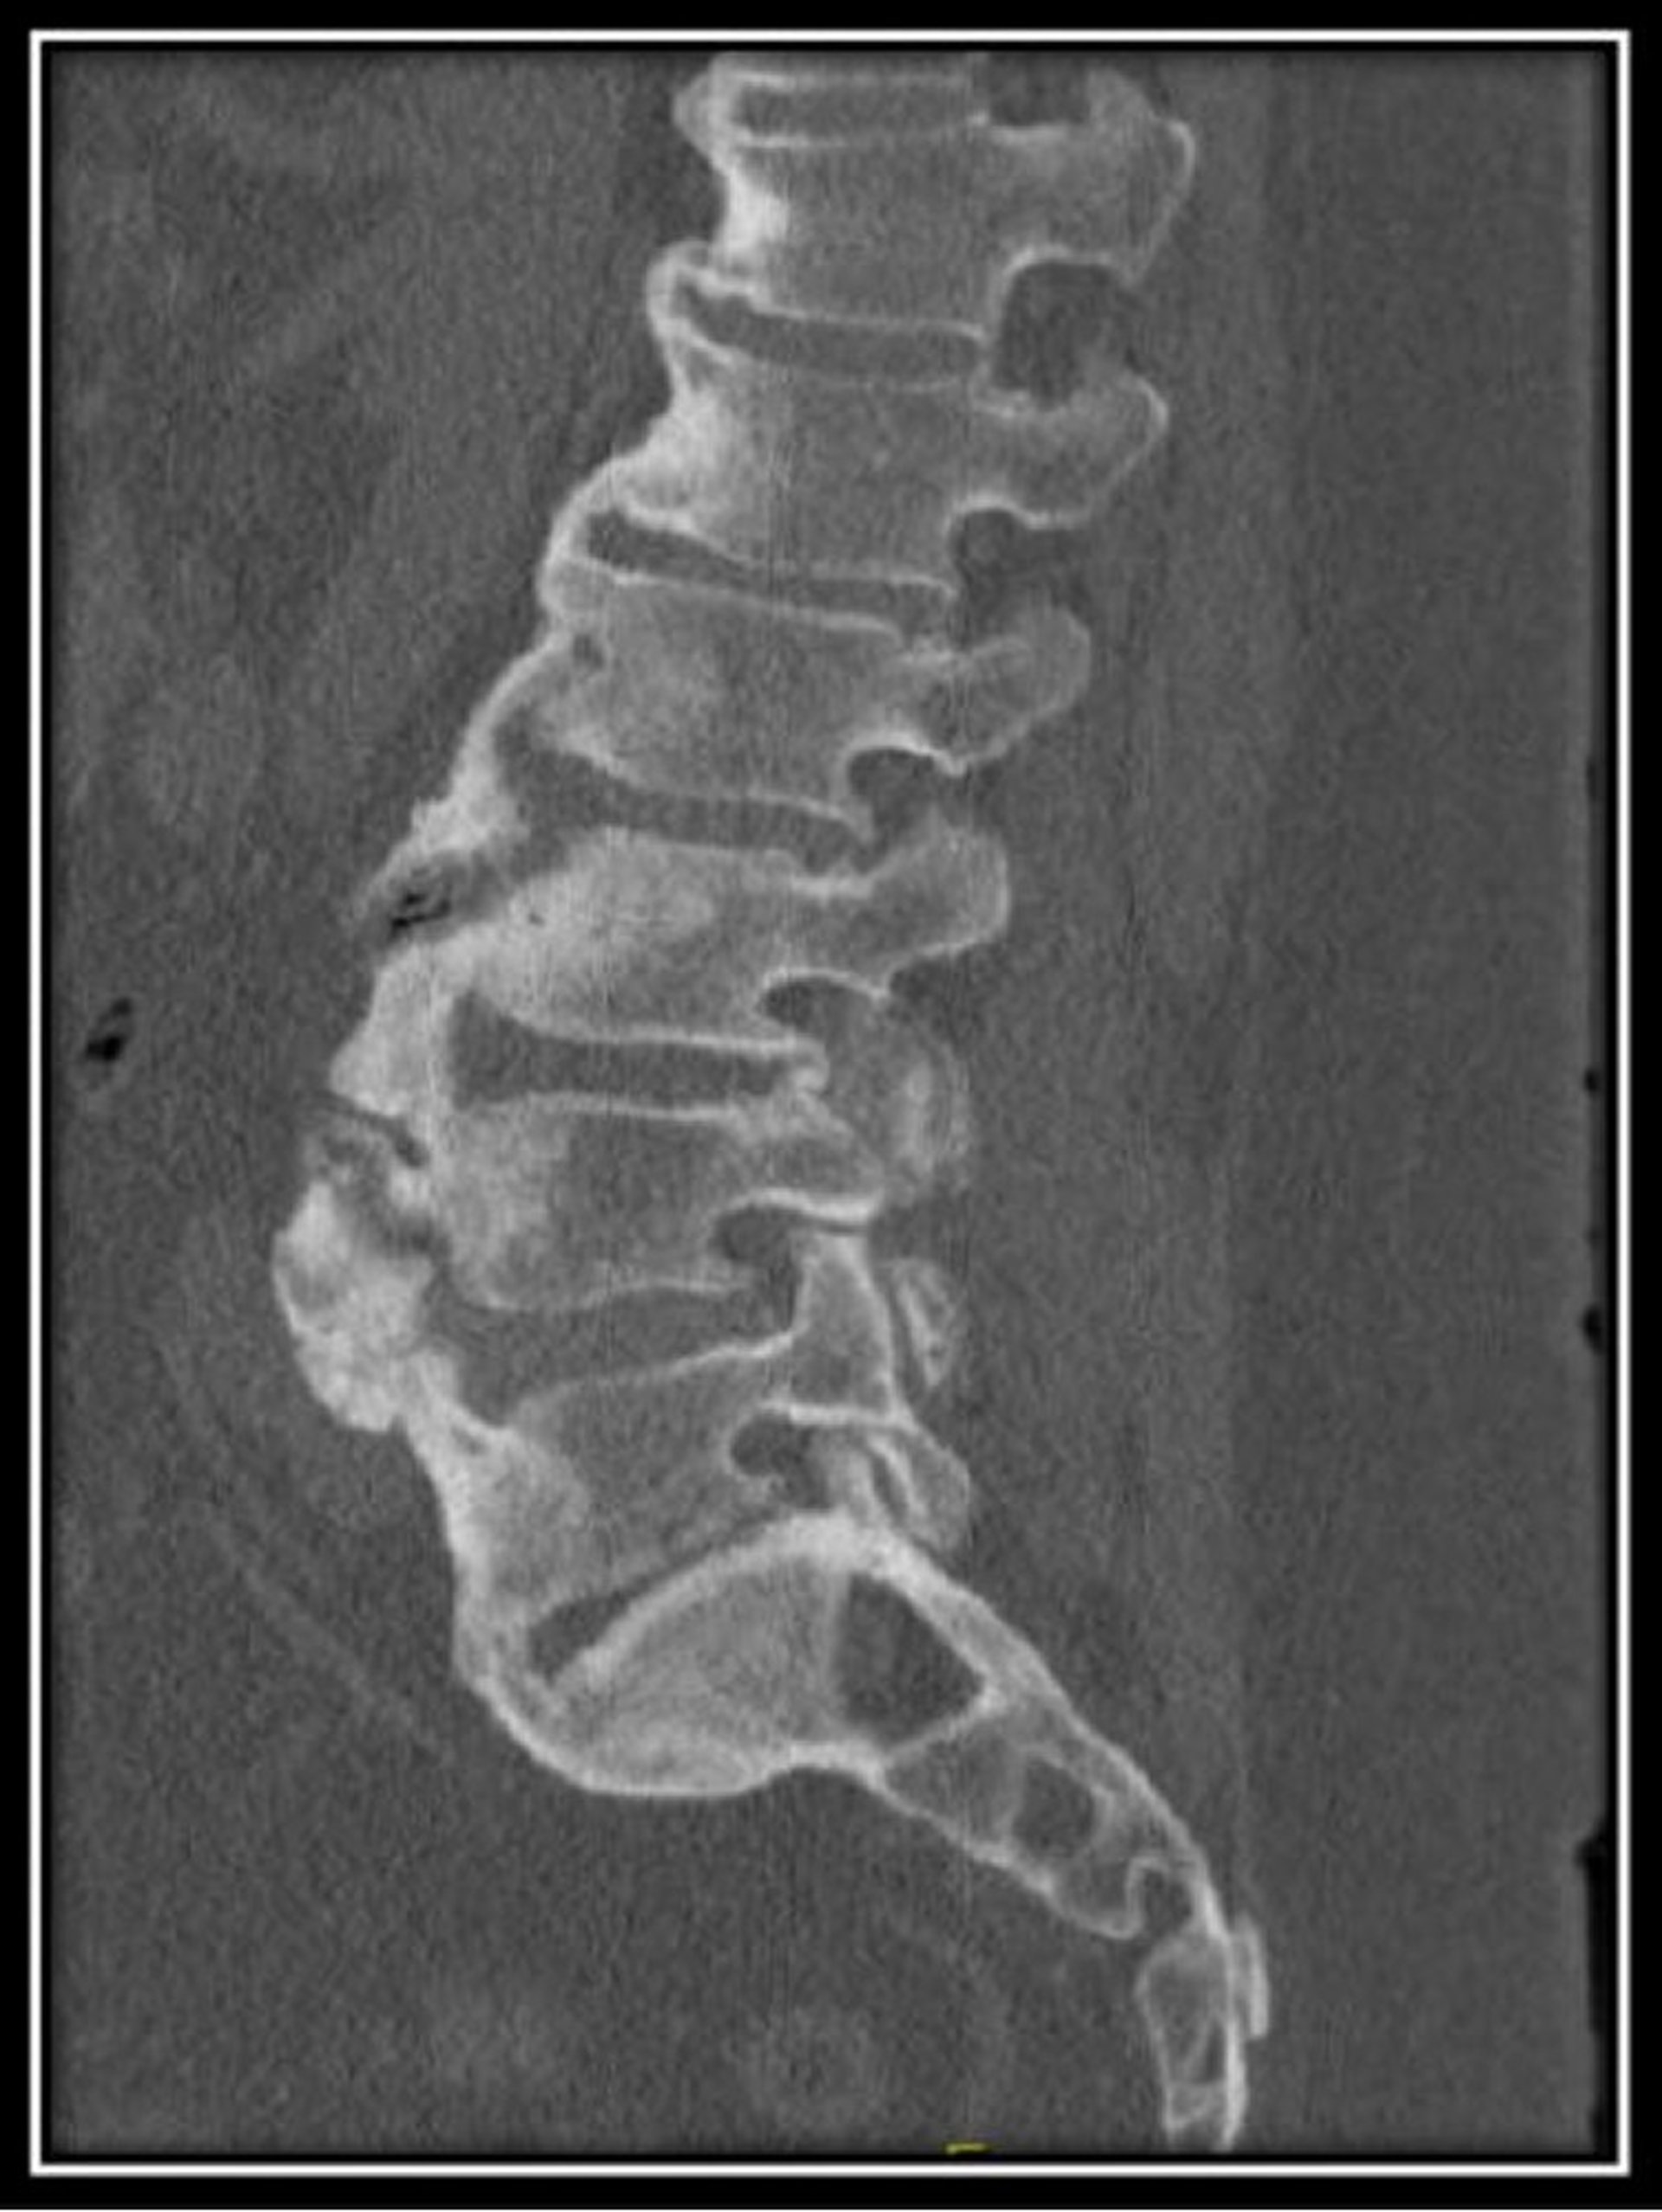

Diffuse Idiopathic Skeletal Hyperostosis (CT Scan)

This CT scan of the lumbar spine in a patient with diffuse idiopathic skeletal hyperostosis shows normal vertebral body heights with diffuse anterior flowing osteophytes with maintained disc spaces.

Image courtesy of Kinanah Yaseen, MD.